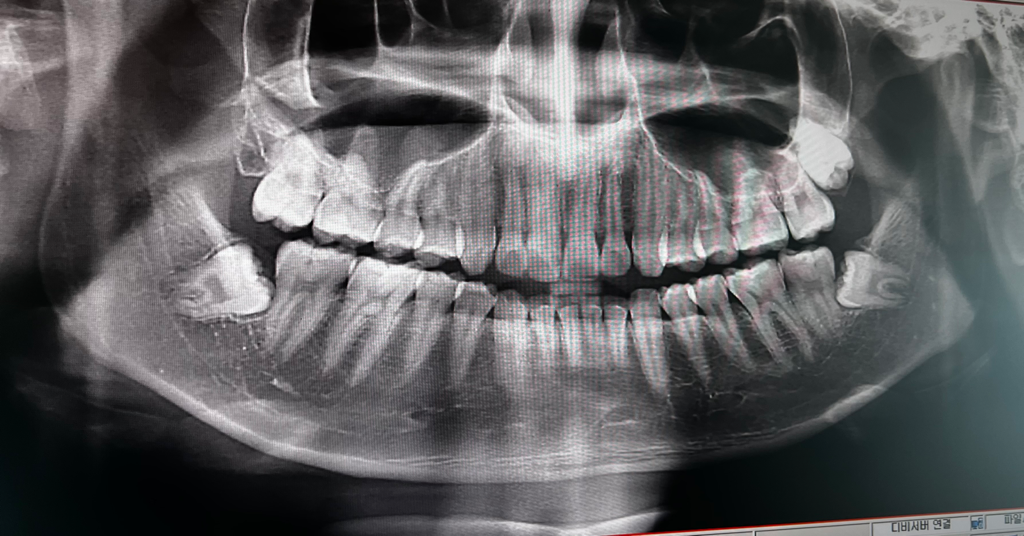

엑스레이 상으로 보면 잇몸이 많이 내려간건 아닌거 같습니다. 크게 걱정은 안하셔도 될것같습니다.

잇몸은 많이 내려가 보이지 않습니다. 부분부분 안좋은 곳도 있지만 앞으로 관리 잘 하시면 괜찮아보입니다.

잇몸은 방사선 사진에선 보이진 않습니다. 다만, 방사선 사진 상에서 잇몸뼈가 아주 심하게 내려앉거나 하지는 않았습니다.잇몸뼈가 녹는 치주염의 상태까지는 아니더라도 치은염은 있을 수 있습니다.